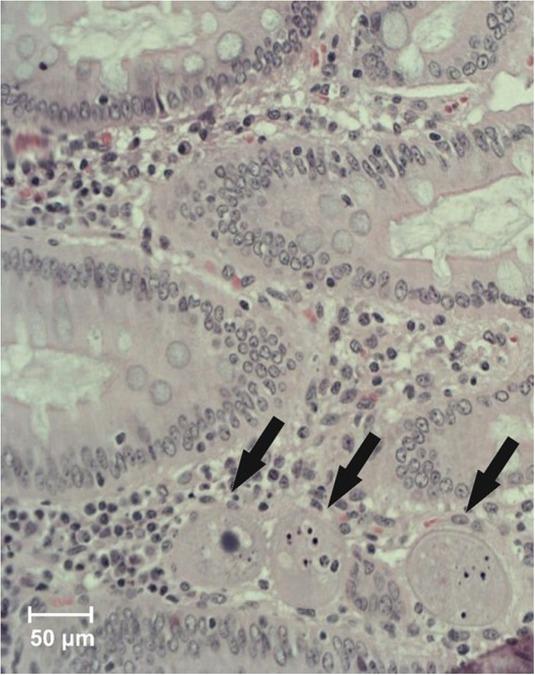

In histological examinations, erosions of caecal and colonic mucosa were found, together with cysts and trophozoites of Balantidium coli. The protozoa were present not only in the intestinal lumen, but also in the intestinal mucosa (Figs 1–3). Parasitological examination with the decantation method confirmed the presence of B. coli cysts in samples of faeces from all examined pigs (Fig. 4). Flotation gave negative results in all samples.

Balantidium coli (arrows) invading colonic mucosa (haematoxylin and eosin, × 200)